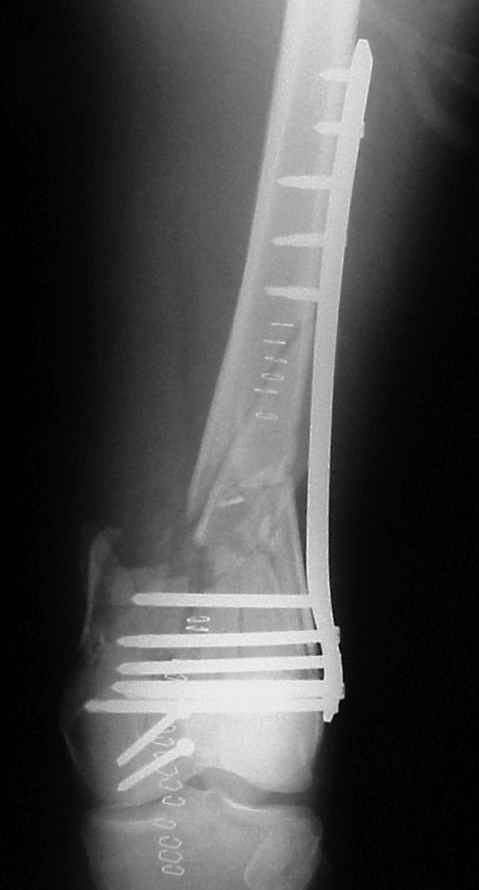

On Wednesday we operated him, we used a LISS plate in either bone, when drillind we had the feeling of a 'normal' bone.

On Thersday afternoon he was alright, he is a very active man and he was moving well both knees. Later that evening he told me that while he was a little bit asleep he turned on the bed and felt pain and that the femur was loose. Here are the X-rays we took.

We are planning to reoperate him on Monday. Removing the screws from the LISS plate and drilling the medial cortex, using locking screws without the drilling tip.

In this case, the fixation might have failed because of inadequate purchase of the side plate to the shaft. I say this because the initial lateral xray shows that the plate seems to be fairly anterior to the mid-axis of the femoral shaft. Once the plate pulled off of the shaft, it continued to pull out of the distal segment. With the short unicortical screws used for shaft fixation, it is imperative that the plate be applied precisely at the midline (widest diameter) of the femur. If it is applied even slightly anterior or posterior to the midline, the screws just don¹t engage the cortex. You can¹t tell by feel, since the screws lock firmly into the plate.

The only guidance that imaging provides is to visualize the plate centered exactly on the bone on a good lateral projection, which is difficult to obtain intra-operatively. I have resorted to making a 3-4 cm incision at the top of the plate so that I can verify that the plate is exactly centered over the femur at its proximal tip.

A second "pearl" is to place at least one or 2 lag screws between the condyles for intrafragmentary fixation before applying the LISS. Although screws were used across the coronal plane (Hoffa) fracture, I do not see any lag screws from lateral to medial. The LISS screws are designed to maintain the reduction of the distal femoral condylar mass to the shaft, but they do not function as lag screws. The intra-articular portion of the fracture demands open reduction and rigid internal fixation according to established

principles; the LISS is used to then stabilize the reconstructed distal femur to the shaft.